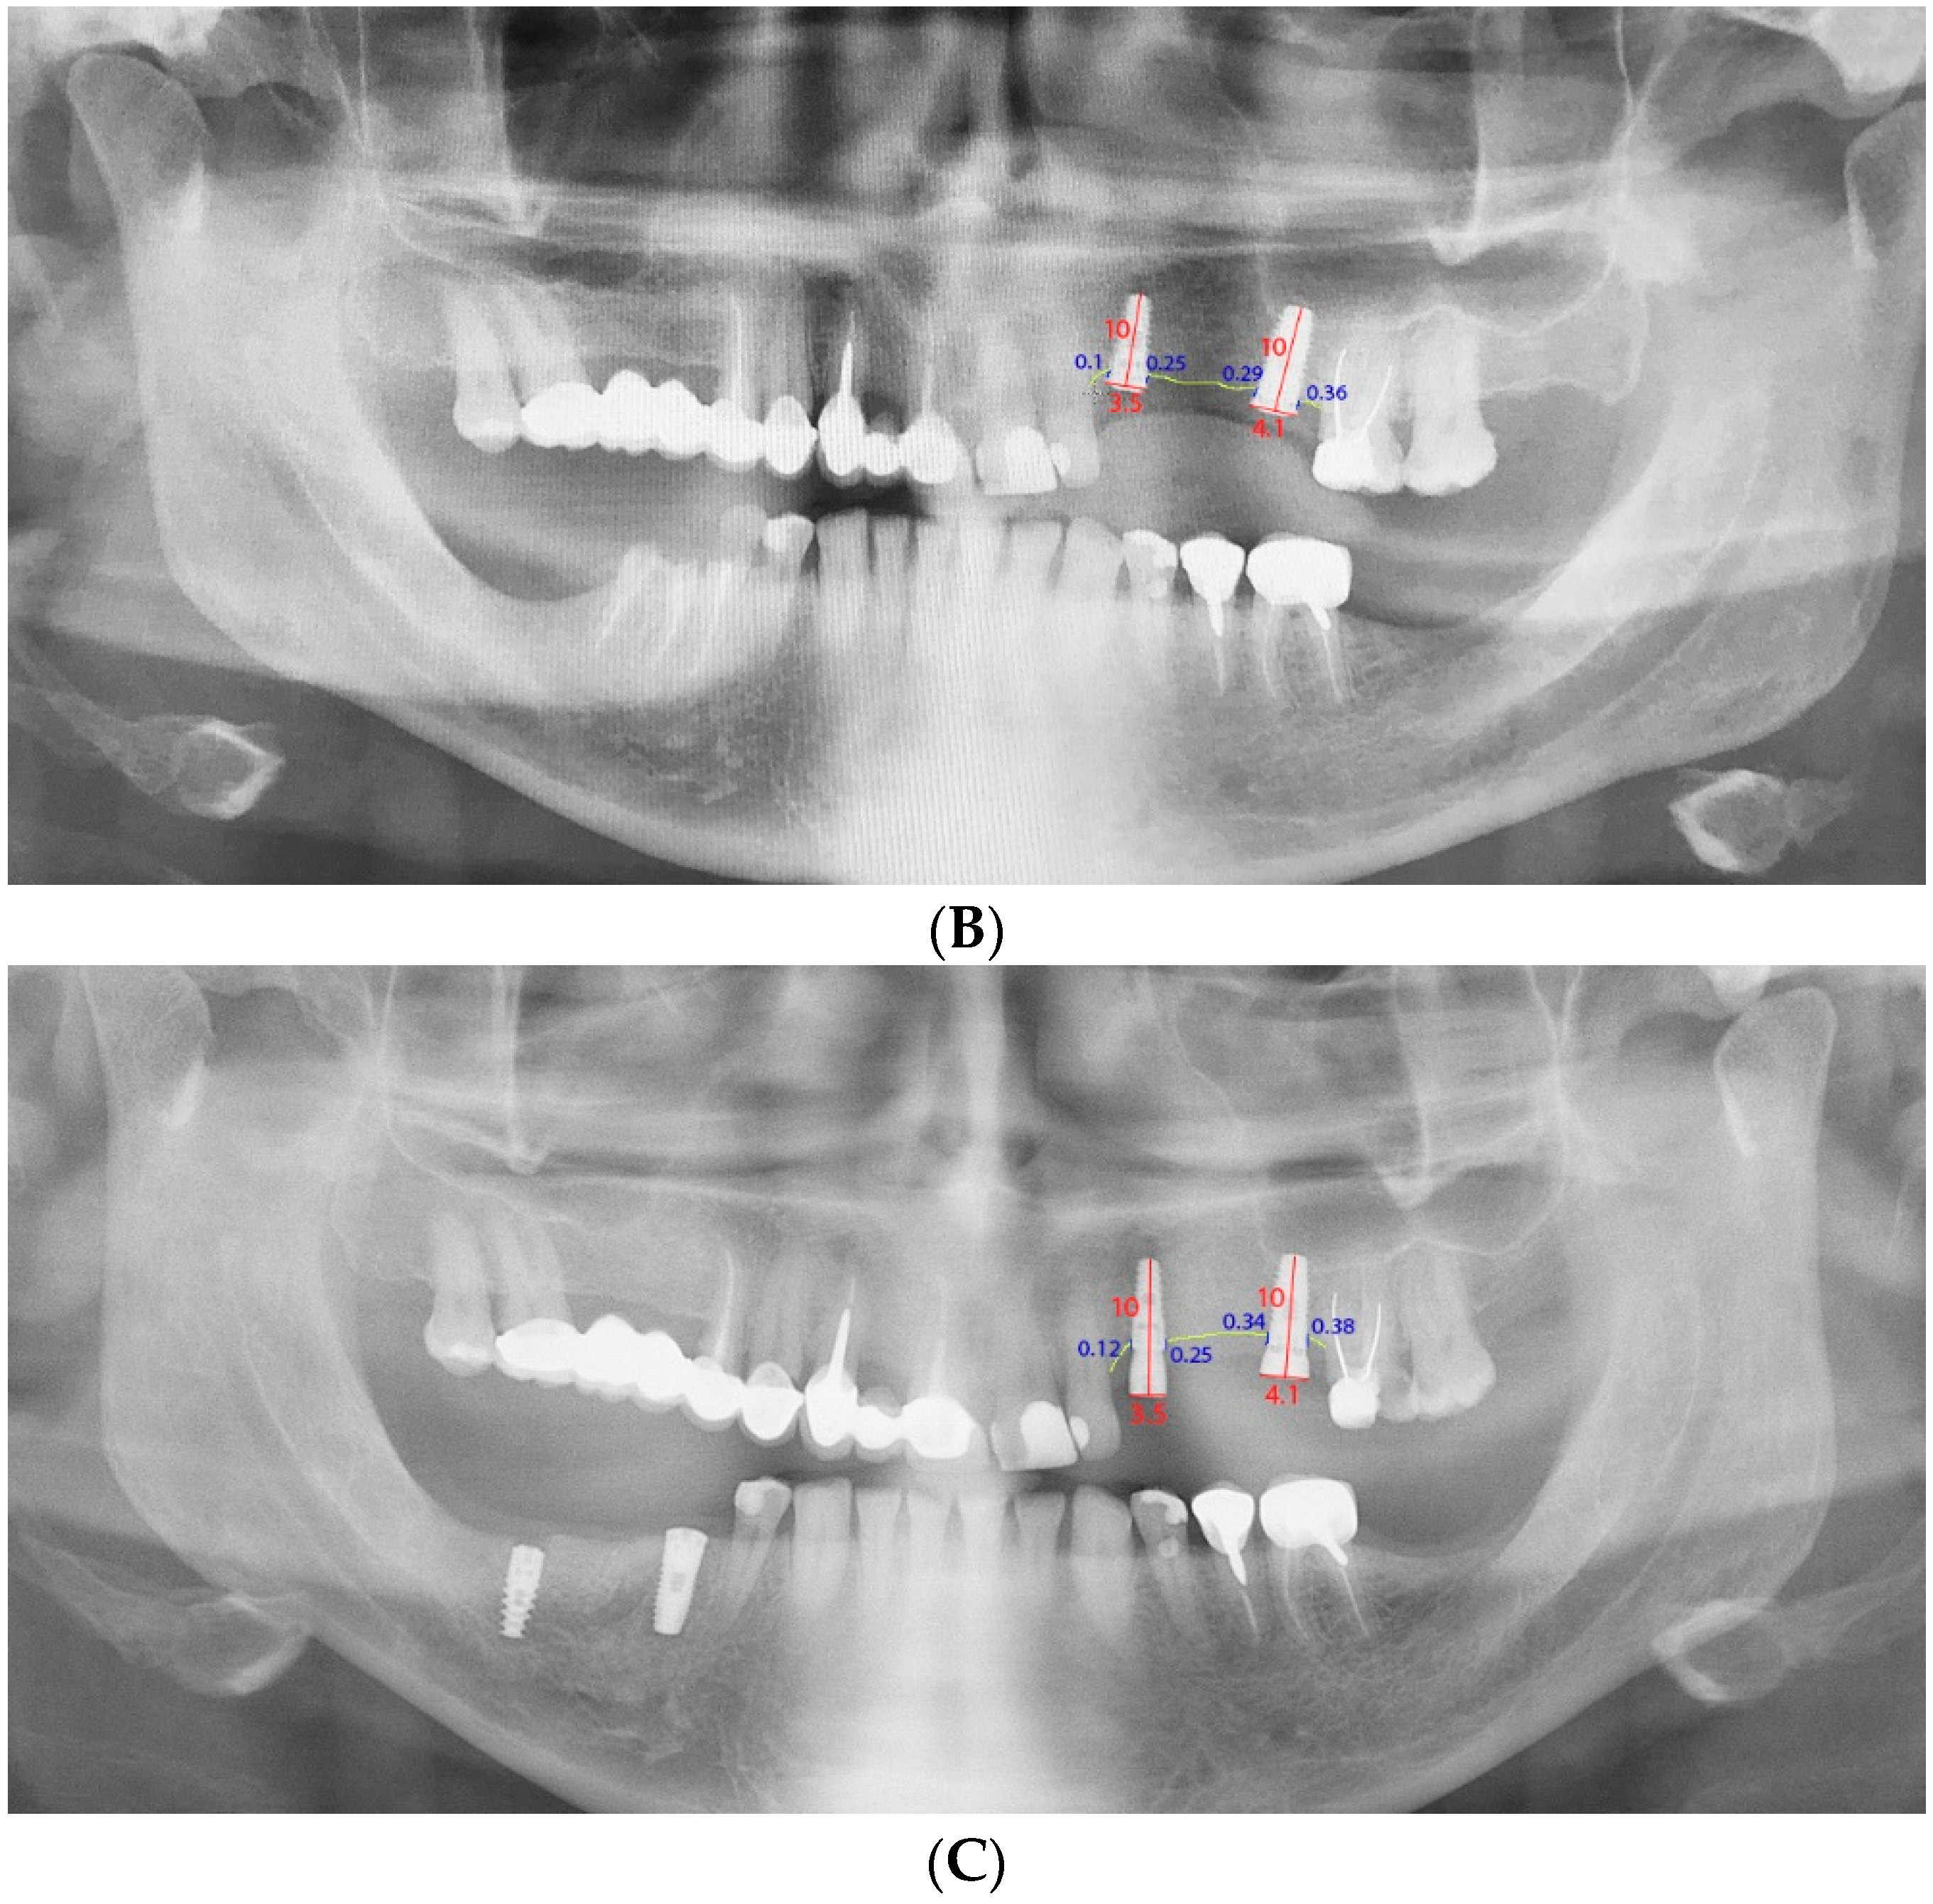

2.7. Radiographic Monitoring of Bone Loss

3.4. Bone Loss